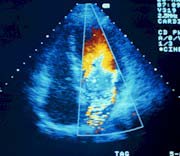

- transtorakalnu ehokardiografiju